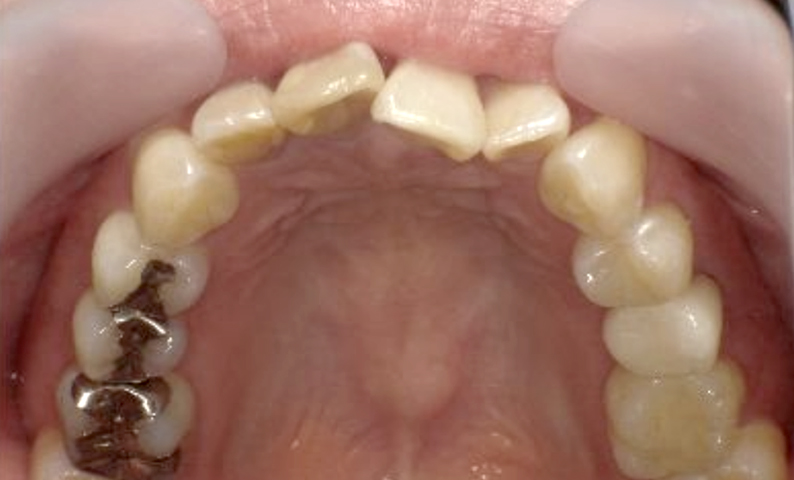

症例_002 上顎だけの部分矯正

治療期間:7ヶ月金額:30万円+税女性前歯のガタガタ上の前歯だけ

| Before | After |